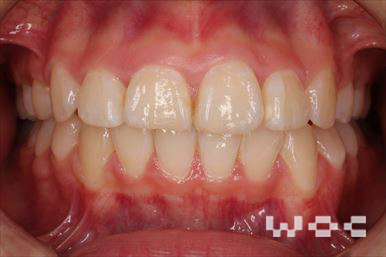

受け口・反対咬合舌側矯正

上下舌側矯正を希望。

通院や歯みがきの協力が良く、上下舌側矯正だったが予定より短い期間で終了しました。-

- 年齢:38歳女性

- 主訴:上下の前歯の先が当たる

- 基本矯正料金:125万円

- 治療期間:1年6ヶ月

- 非抜歯